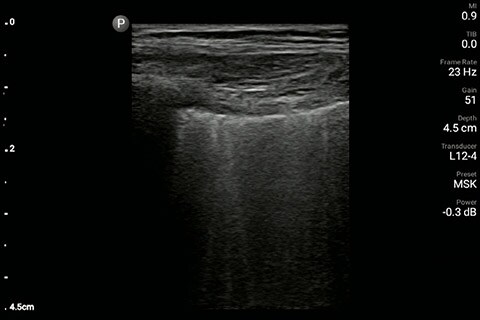

In this Lumify case study and summary video, Dr. Sara Nikravan discusses how she used her Philips Lumify handheld ultrasound system to guide the diagnosis and treatment of a patient experiencing shortness of breath.

Determining the cause of respiratory distress in the acutely ill can be challenging. POCUS with a three-point exam (F-TTE, IVC collapsibility, and lung ultrasound), as performed above, has been endorsed in this patient population as it can increase diagnostic accuracy in a timely fashion, especially as it pertains to acute decompensated heart failure.4 Furthermore, the use of a small portable device allows for convenience with rapid setup and use while minimizing the uptake of space. This becomes especially important when caring for patients that often have many providers attempting to provide care and initiate interventions at the same time, given the acute nature of their illness and potential for further rapid de-compensation.